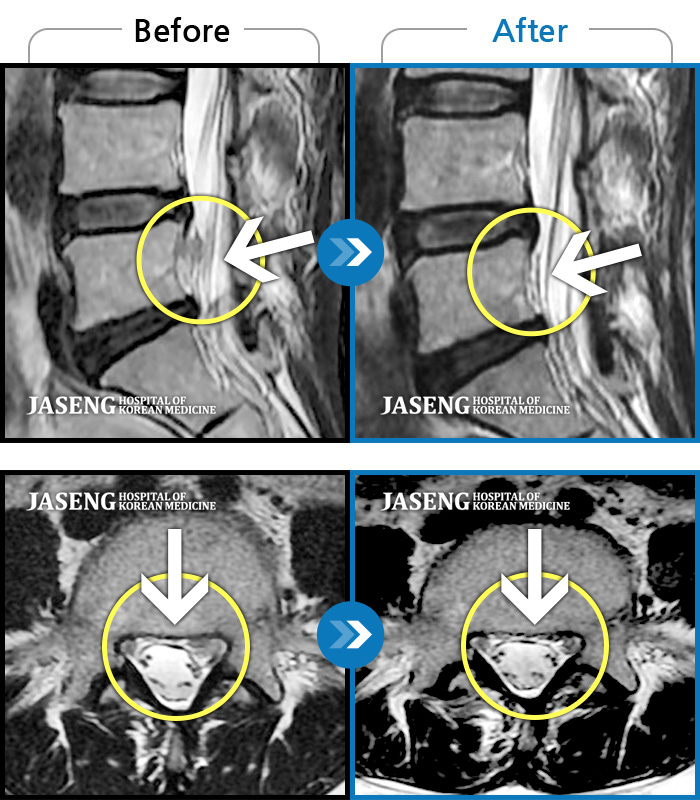

푸쉬업을 여러 번 반복한 뒤 극심한 하요부 통증 및 우측 하지부 저림